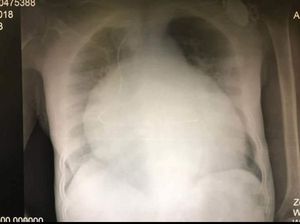

Dx ??

Enlargement of heart

Cardiac tamponade

Tamponade

Precardium effusion